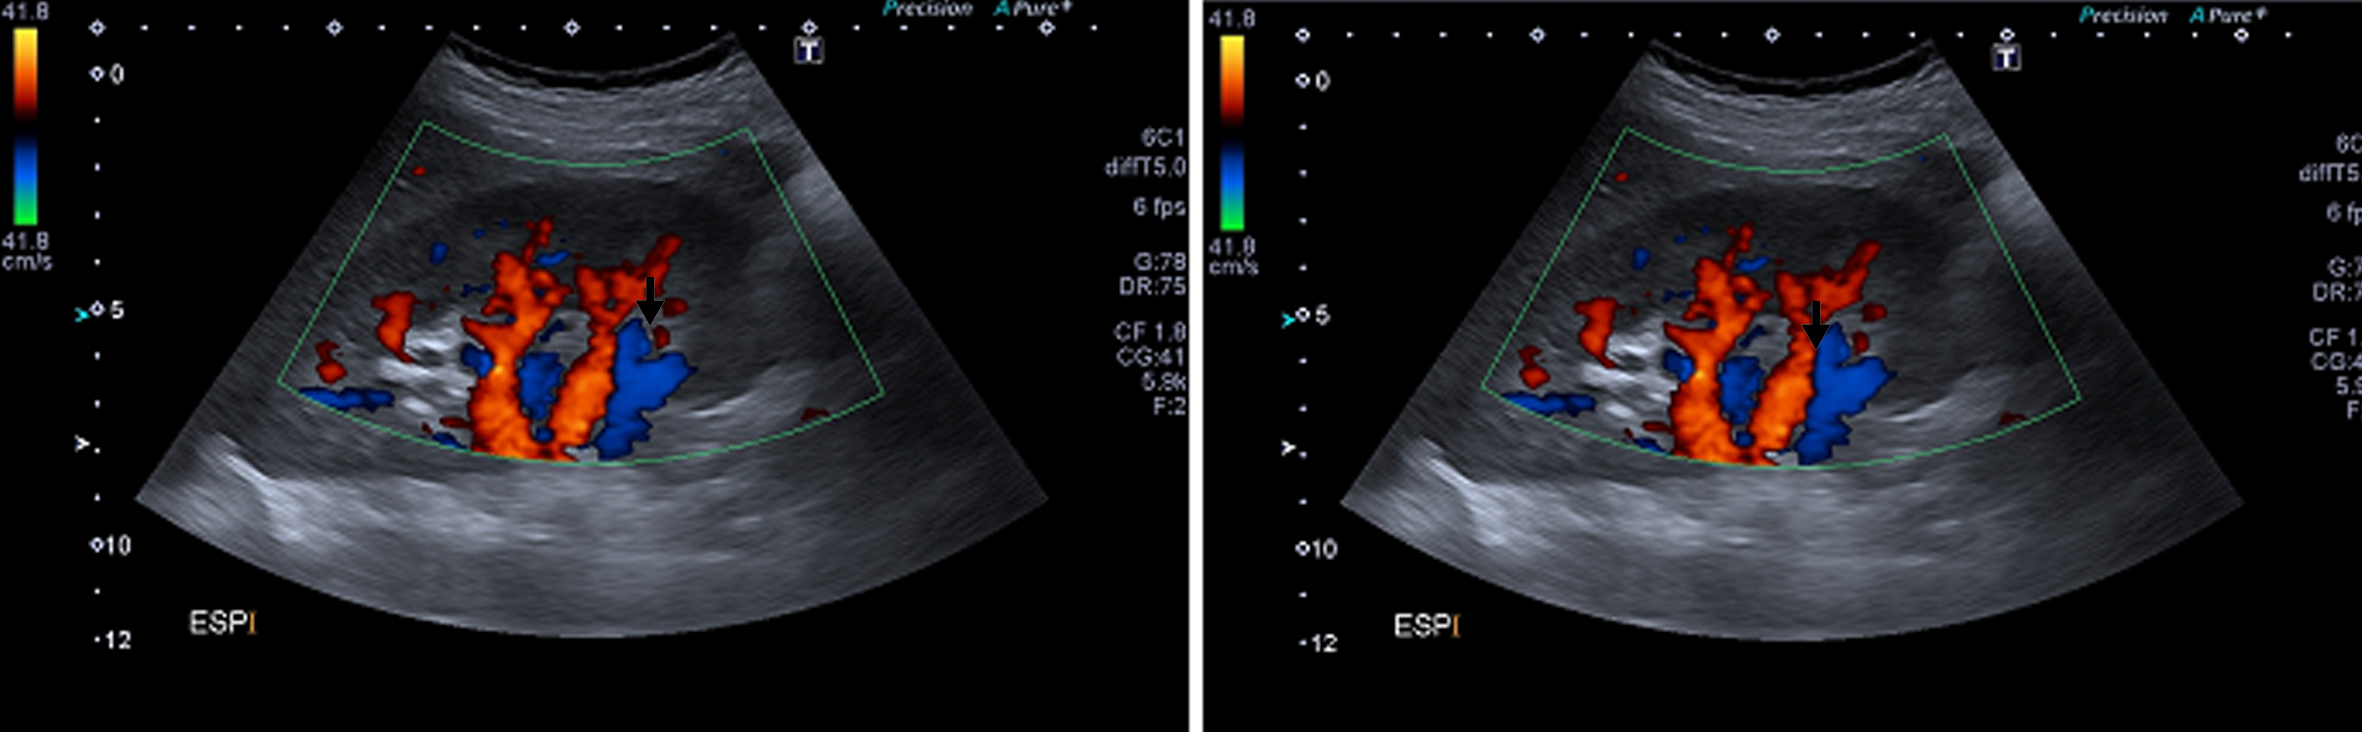

Posteriormente se realiza ecografía Doppler color de las arterias renales a efectos de valorar el patrón hemodinámico en las mismas, particularmente en la arteria renal derecha, y evidenciar en tiempo real cambios en dicho patrón vinculados a la fase del ciclo respiratorio (estudio dinámico).

Se comprueba una aorta abdominal ectásica en toda su extensión, con velocidades sisto-diastólicas habituales (velocidad picosistólica de 70 cm/seg.). Ambos riñones son de forma y tamaño habitual, con parénquima de espesor y ecogenicidad normal y buena diferenciación córtico-medular bilateralmente. No se ven alteraciones de las cavidades excretoras. Se realiza estudio dinámico de las arterias renales durante el ciclo respiratorio el cual demuestra que durante la inspiración el sector proximal de la arteria renal derecha se “verticaliza”, quedando paralela a la aorta abdominal, (Fig. 5), comprobándose además aumento de las velocidades sisto-diastólicas en este sector de la arteria, con velocidades picosistólicas (VPS) de 385 cm/seg en inspiración, comportándose desde el punto de vista hemodinámico como una estenosis significativa.

En esta fase del ciclo se observa íntimo contacto entre el sector proximal de la arteria renal derecha y la crura diafragmática ipsilateral, en concordancia con lo visto por angioTC.

Durante la inspiración es también evidente una disminución significativa de la vascularización del riñón derecho, con ondas de flujo de tipo “tardus et parvus” a nivel intrarrenal compatible con flujo post-obstructivo (postestenótico). (Fig. 6)

En espiración la arteria tiene un trayecto horizontal y velocidades de flujo normales (VPS de 122 cm/seg) (Fig. 5), siendo la vascularización intrarrenal de distribución habitual y con patrones de flujo normales. (Fig. 4)

Figura 5

Ecografía Doppler En espiración (izquierda) y en inspiración (derecha). (flecha negra) Arteria renal derecha.